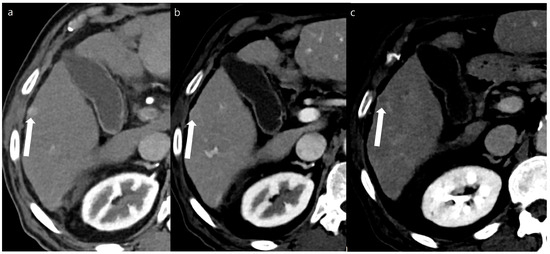

Figure 2. A 65-year-old man with a 0.8 cm sized hepatocellular carcinoma at segment 5 of the liver (arrows). Arterial phase (a), portal phase (b), and delayed phase (c) images of a double low-dose CT using a deep-learning-based contrast-boosting model show a well-enhancing nodule on the arterial phase (a), with washout on the portal phase (b) and the delayed phase (c).